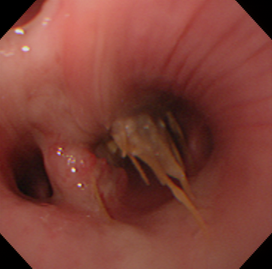

Some gastric FBs, such as bones or potatoes, do not need removal as they will be digested, yet they will need to be removed if they are stuck in the oesophagus. Also, it may not be safe to try to remove sharp objects endoscopically. Ingested fishhooks often lie free in the GI lumen and are retrieved by gripping the curved part so that the hook is pointing backwards (Figure 1). If the barb is lightly embedded in the mucosa, it may be possible to rip it out, but if it is more deeply embedded, which is likely if someone has yanked on the fishing line exiting the mouth, it may be possible to force it forward, back into the lumen. However, surgical removal may be needed.